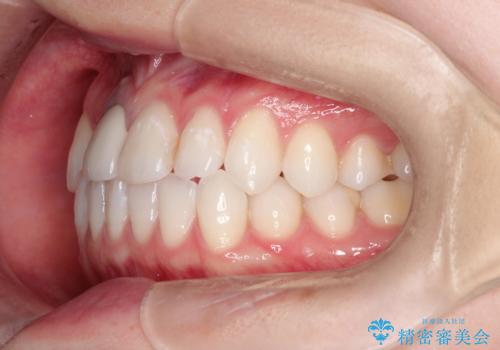

- 前歯の凸凹を主訴に来院されました。

インビザラインにて短期間で満足いく結果が得られたと大変喜ばれました。

歯と歯の間に僅かなスペースを作って配列していました。追加アライナーを1回行っています。